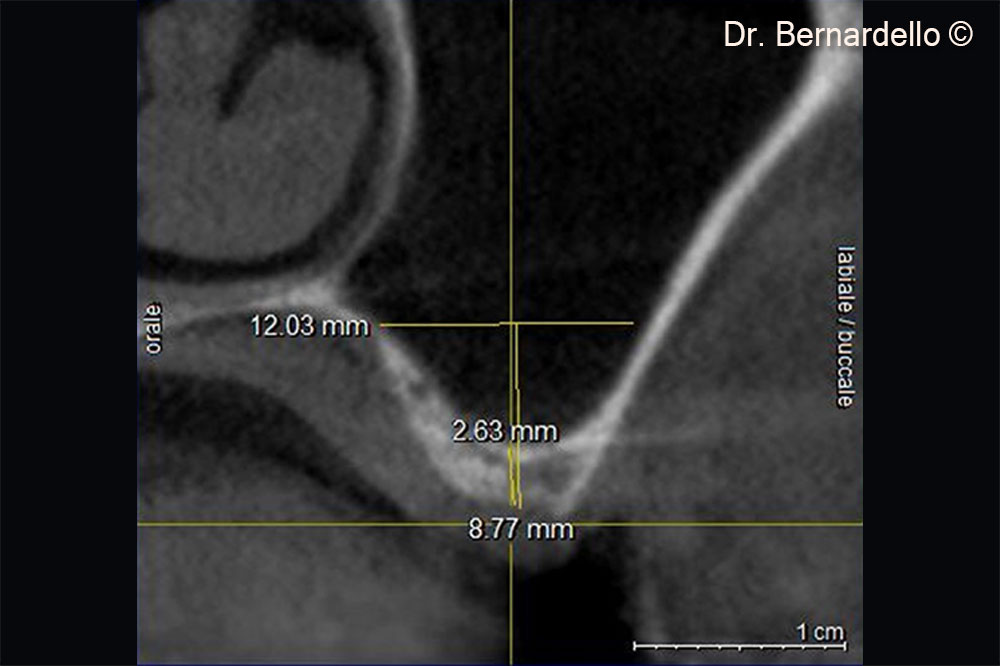

Dựa trên chiều rộng xoang, bệnh nhân nữ (55 tuổi) được coi là đủ điều kiện để thực hiện phẫu thuật nâng sàn xoang qua mào xương.